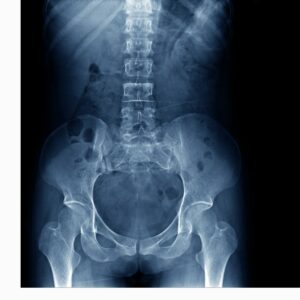

The human spine is a complex structure made up of vertebrae, intervertebral discs, ligaments, muscles, and nerves. Its role in supporting body weight, enabling mobility, and protecting the spinal cord makes it central to everyday function.

However, due to aging, injury, poor posture, and degenerative diseases, spinal conditions are among the most frequent musculoskeletal complaints. This article explores the most common spinal conditions and the treatment options available, ranging from conservative therapies to surgical interventions.

4. Scoliosis

Overview

Scoliosis is a lateral curvature of the spine that typically develops during adolescence but can also occur in adults due to spinal degeneration (adult-onset scoliosis).

8. Ankylosing Spondylitis (AS)

AS is a chronic inflammatory disease affecting the spine and sacroiliac joints. Over time, it can lead to the fusion of spinal vertebrae.